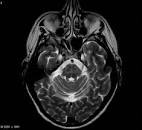

Multiple System Atrophy (MSA)

Multiple System Atrophy (MSA),does not have any definitive cure anywhere. However, Ayurveda treatment is known to help in managing the symptoms better